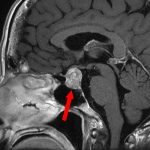

711

'25年12月

60代

良性頭蓋咽頭腫

頭蓋内腫瘍摘出術